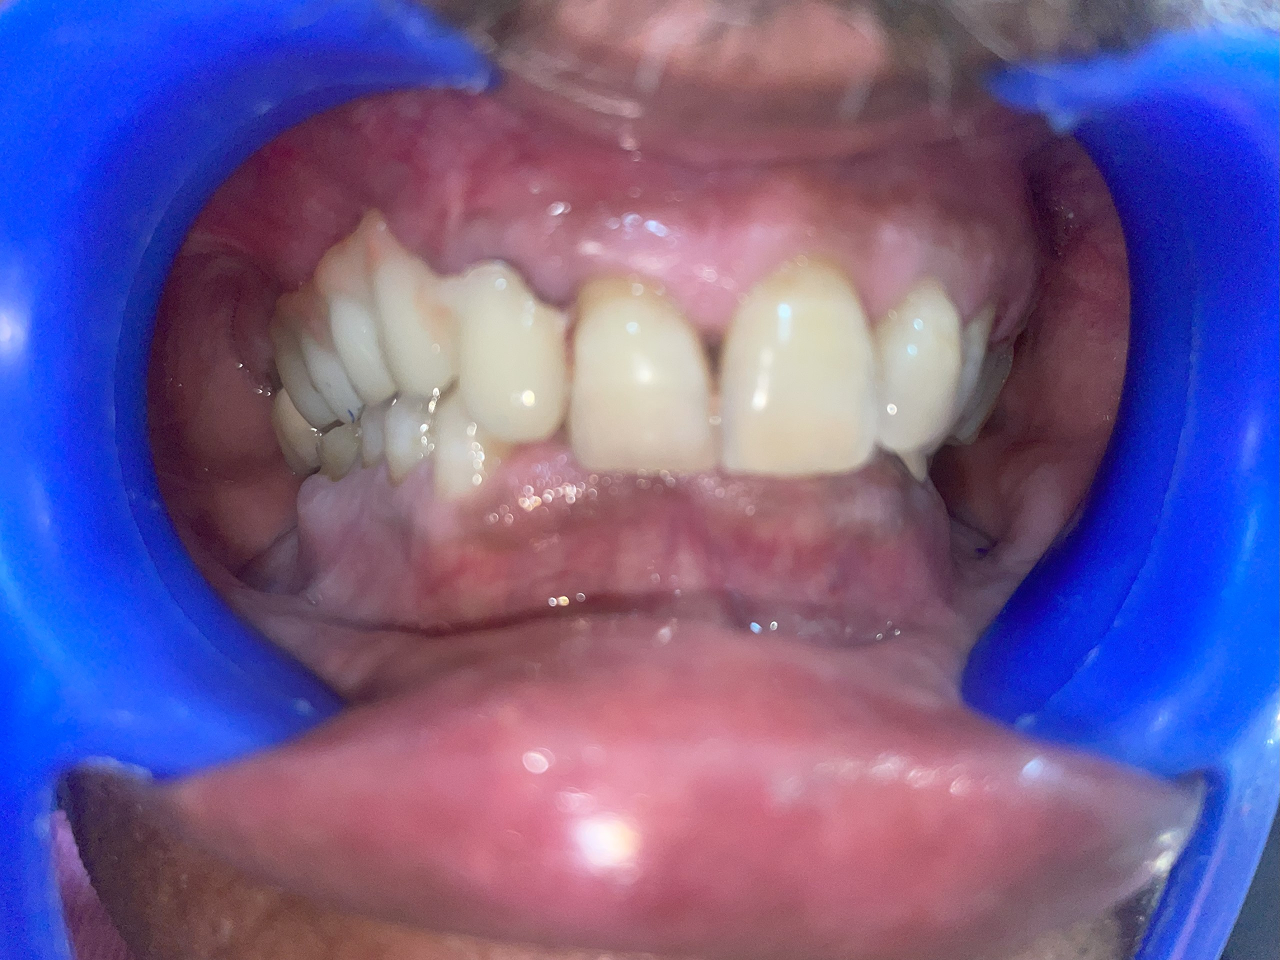

Full Mouth Rehabilitation

This includes comprehensive dental work such as implants, crowns, root canals, and other restorations to fully restore dental health and aesthetics.

After treatment